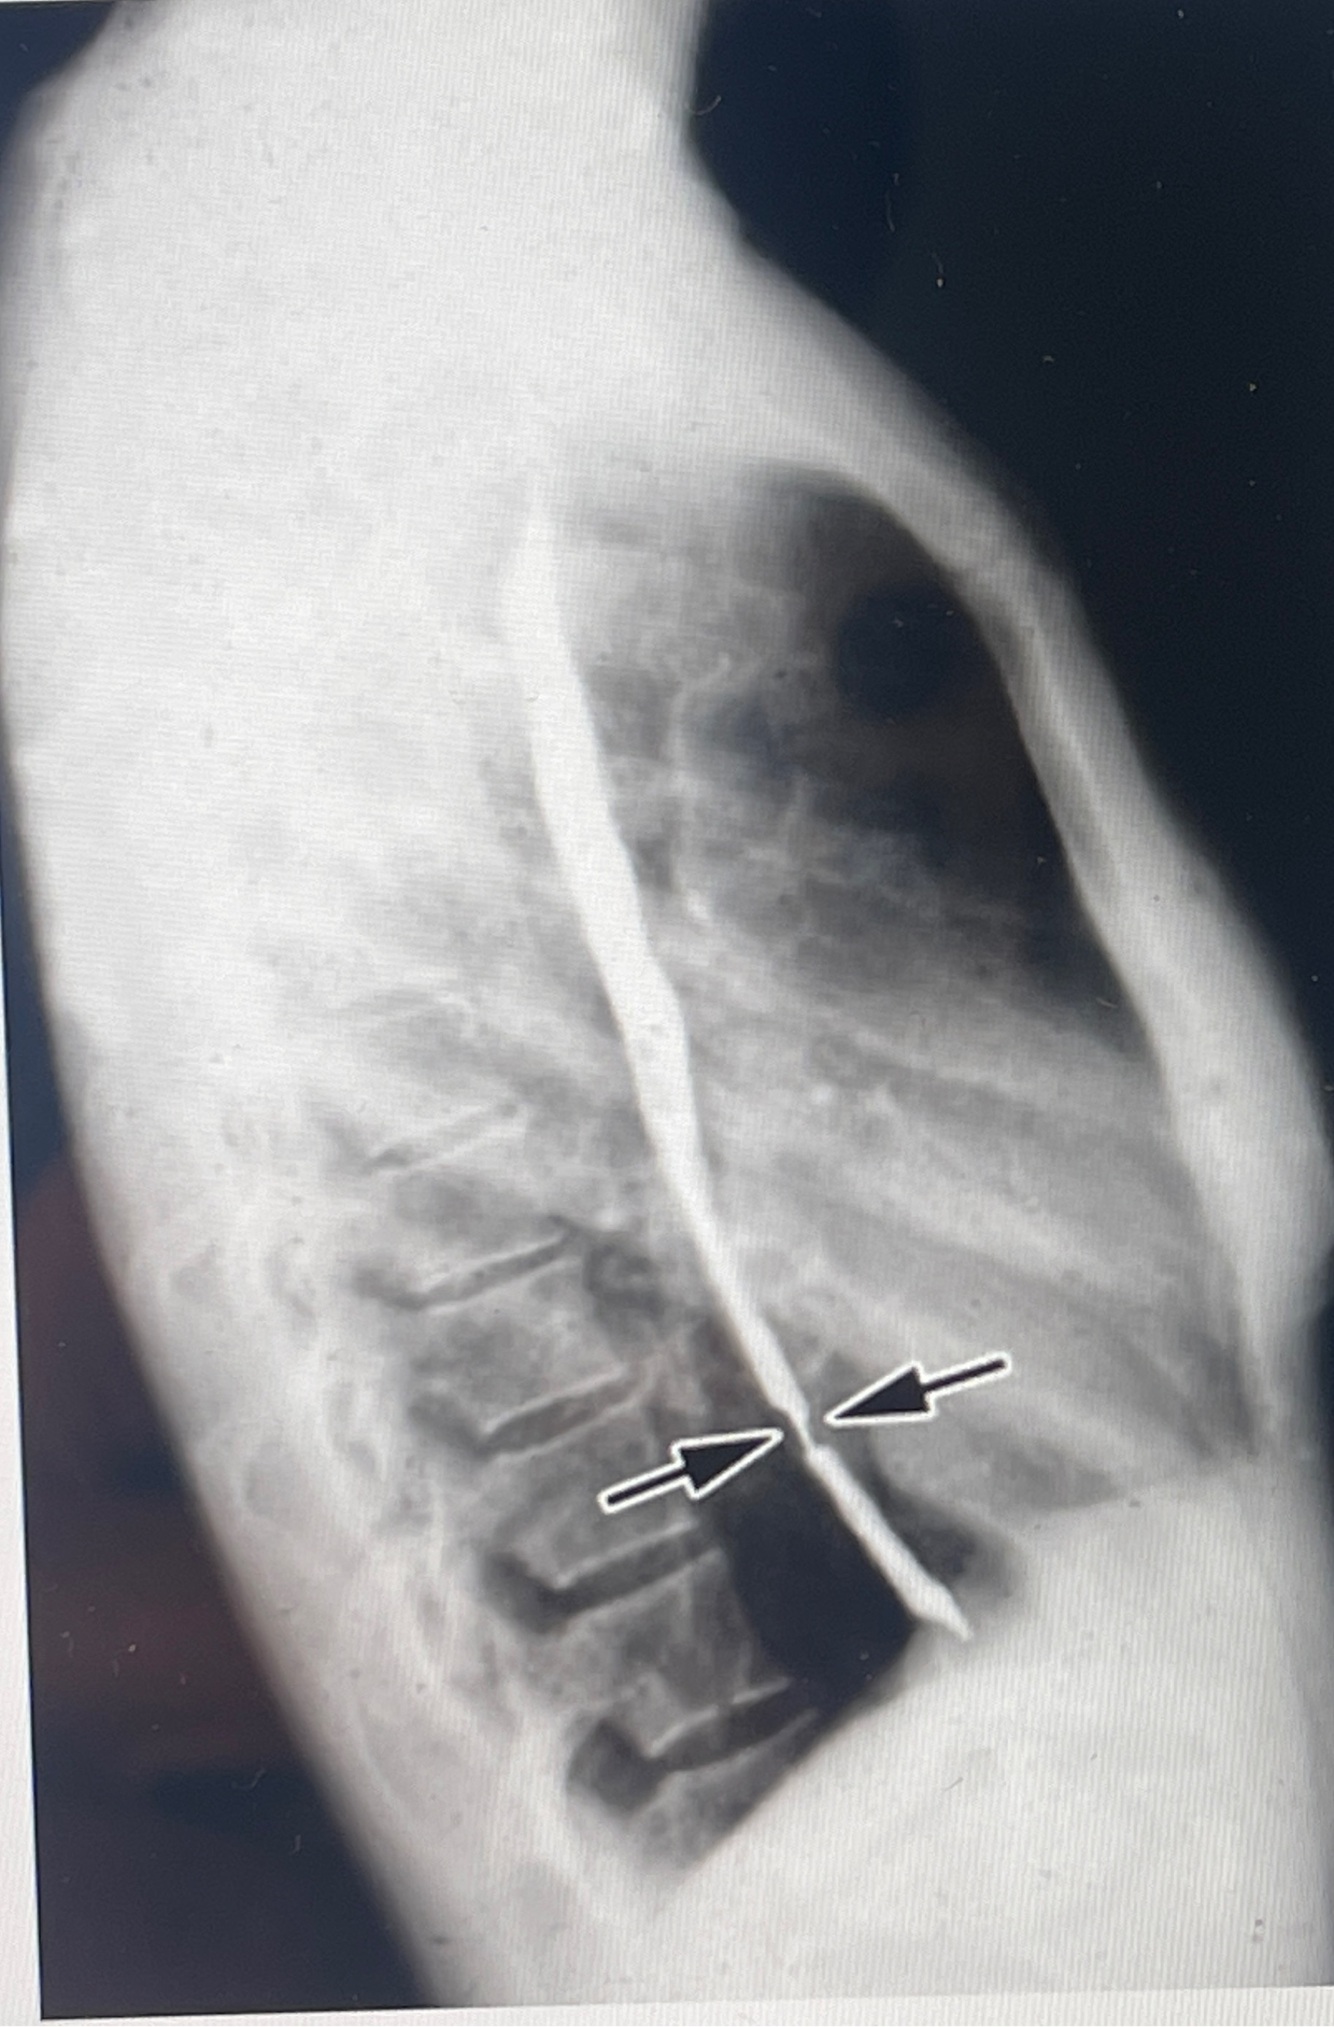

Q

A

How well did you know this?